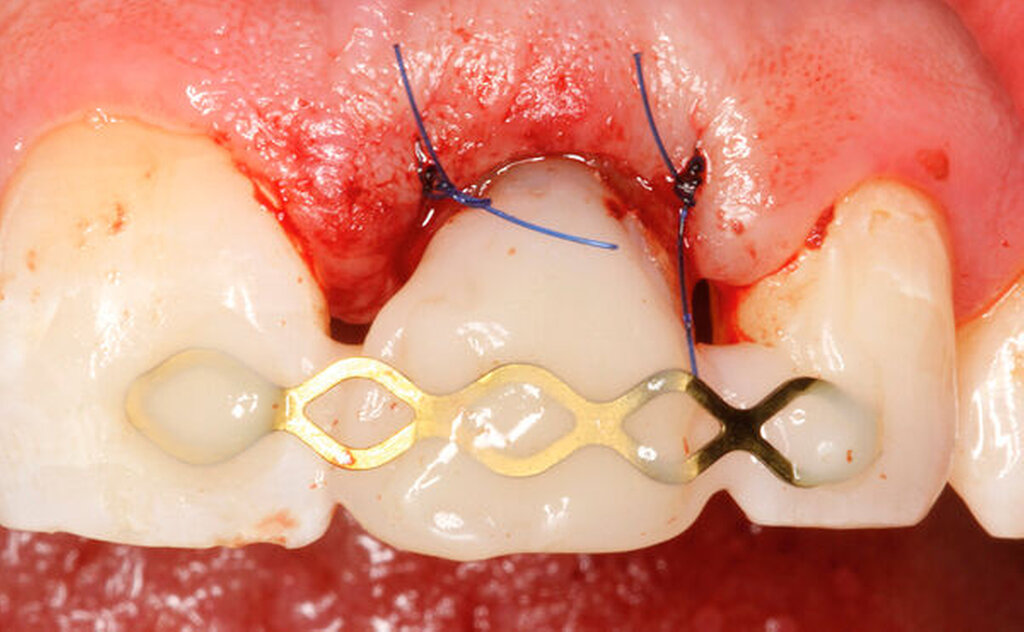

Eine weitere Möglichkeit, tief zerstörte Zähne möglichst schonend chirurgisch zu extrudieren, basiert auf axialen Zugsystemen (Abbildungen 2 bis 4). Diese erscheinen vorteilhaft bei sehr schwierigen Fällen, zum Beispiel bei Zähnen mit fehlendem Ansatzpunkt für die Zange sowie bei langen oder sehr ovalen Wurzeln. Axiale Zugsysteme ermöglichen die Übertragung von Zugkräften auf die Zahnwurzel, ohne die Alveole unnötig zu dehnen. Dazu wird eine spezielle Schraube in den Wurzelkanal eingebracht und das Gewinde der Schraube für eine ausreichende Friktion fingerfest eingedreht. An diese Schraube wird ein gerätespezifisches Zugsystem angelegt. Durch rein axial wirkende Zugkräfte werden traumatische Effekte auf Knochen und Wurzeloberfläche während der Zahnmobilisation minimiert. Gegebenenfalls können feine Luxatoren vorsichtig unterstützend eingesetzt werden. Im Tiermodell wurde an extrahierten und wieder replantierten Zähnen mit ovalem Querschnitt gezeigt, dass der Verlust von Zementoblasten auf der Wurzeloberfläche geringer ist, wenn ein axiales Zugsystem anstatt einer Extraktionszange verwendet wird.

Als Vorteil der chirurgischen Extrusion im Vergleich zur chirurgischen Kronenverlängerung wird das deutlich vorteilhaftere ästhetische Resultat mit Erhalt von Weichgewebe und Papille angegeben [Llaquet et al., 2021]. Diese Gewebe werden geschont und erfahren keine Traumata, wie dies bei einer chirurgischen Kronenverlängerung unvermeidbar geschieht [Behring et al., 2017; Lanning et al., 2003]. Indiziert ist die Extrusion vor allem bei einwurzeligen Zähnen in ästhetisch relevanten Bereichen. Biologisch betrachtet liegen solide und langzeitstabile Resultate zu dieser Technik vor. Einer aktuellen Übersichtsarbeit zufolge, basierend auf elf klinischen Studien, kann ein Behandlungserfolg mit parodontaler Heilung der Wurzel in 95 bis 100 Prozent der Fälle nach chirurgischer Extrusion erwartet werden [Plotino et al., 2020]. Eine weitere Übersichtsarbeit fokussiert auf die Häufigkeit von Komplikationen nach chirurgischer Extrusion. Den verfügbaren Daten zufolge liegt das Risiko für Zahnverlust bei fünf Prozent, das für progressive Wurzelresorptionen bei drei Prozent. Ein marginaler Knochenabbau ist ebenfalls eine seltene Komplikation (weniger als vier Prozent der Fälle). Nicht progressive Wurzelresorptionen werden mit circa 30 Prozent zwar recht häufig beobachtet, diese sind allerdings selbstlimitierend und gefährden nicht den Zahnerhalt [Elkhadem et al., 2014].

Eine sehr gewebeschonende, jedoch zeitlich aufwendigere Technik zur Generierung eines Ferrule-Effekts bei tief zerstörten Zähnen ist die kieferorthopädische Extrusion [Bondemark et al., 1997; Brandt, 2016; Krastl, 2004; Carvalho et al., 2006; Hergt und Christofzik, 2017; Mehl et al., 2017; Wirsching, 2011]. Diese Technik ist prädestiniert für die ästhetische Zone, da hier im Gegensatz zu anderen invasiveren Techniken kein Gewebeverlust auftritt. Vielmehr kann durch den langsamen Extrusionszug vermittelt über den parodontalen Faserapparat eine Migration des Hart- und Weichgewebes (falls gewünscht) induziert werden. Wird während der Extrusionsphase das parodontale Ligament regelmäßig durchtrennt, findet folglich keine Gewebsmigration statt [Carvalho et al., 2006].